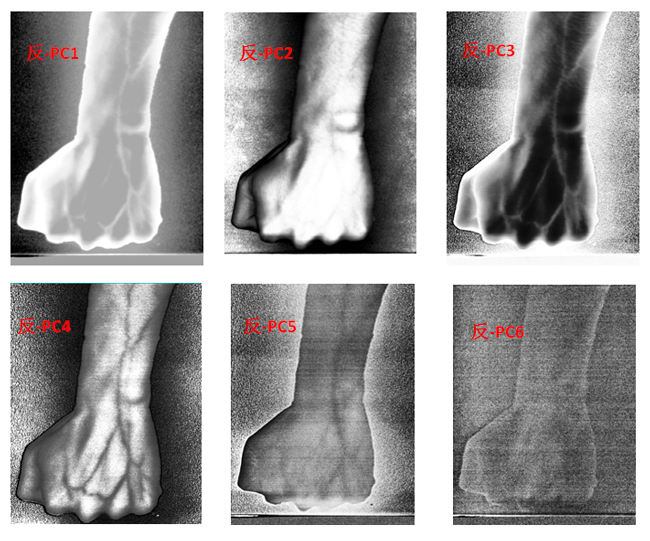

為了客觀地識別手臂上的靜脈,對經(jīng)預(yù)處理后的高光譜數(shù)據(jù)進(jìn)行主成分分析(Principal Component Analysis, PCA),去除波段之間的多余信息、將多波段的圖像信息壓縮到比原波段更有效的少數(shù)幾個轉(zhuǎn)換波段下。圖9為手臂正反面經(jīng)PCA變換后的前6個主成分。

圖9 手臂正反兩面PCA處理后的前6個主成分